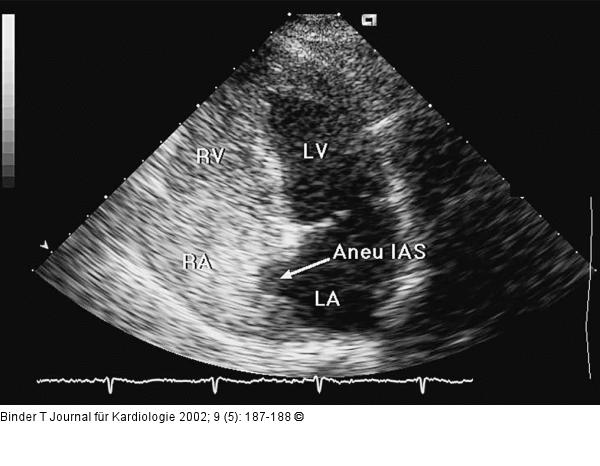

Abbildung 4: Interatriales Septum - Aneurysma Venöse Kontrasmittelapplikation (5,5 % Oxypolygelatine). Der rechte Vorhof (RA) und der rechte Ventrikel (RV) sind im KM ausgefüllt. Lediglich im Bereich des Aneurysmas bleibt eine Aussparung. LA = linker Vorhof, LV = linker Vorhof. |

Abbildung 4: Interatriales Septum - Aneurysma

Venöse Kontrasmittelapplikation (5,5 % Oxypolygelatine). Der rechte Vorhof (RA) und der rechte Ventrikel (RV) sind im KM ausgefüllt. Lediglich im Bereich des Aneurysmas bleibt eine Aussparung. LA = linker Vorhof, LV = linker Vorhof. |